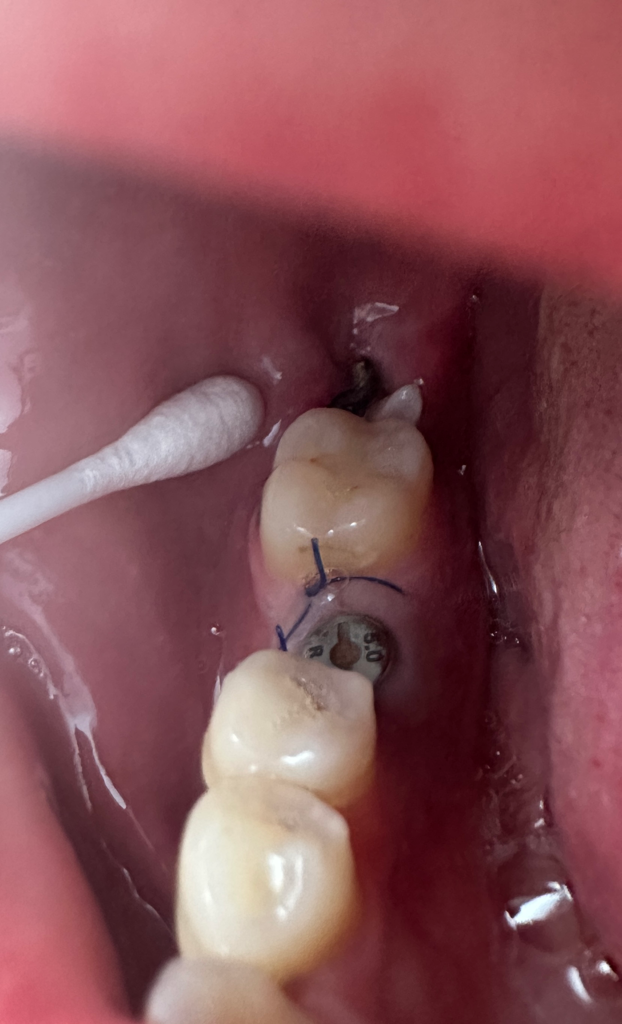

매복 사랑니 발치6일차인데 무슨 뼈 같은게 보여요

매복사랑니 발치한 부분 꿰맨 부분 옆으로

무슨 뼈같은게 튀어나와있고 좌우로 막 움직입니다

이 하얀거 막 건드리면 움직이는데 손으로 그냥 뽑아도 되나요 ㅠㅠ? 좌우로 움직여서 거슬려요..

아님 염증이 심해서 이게 생긴걸까요...?

매복사랑니 발치시 잇몸뼈 조각일수도 있을것같습니다. 치과에 가셔서 제거를 해달라고 하시면될것같습니다.

말씀만 들어서는 정확히 알 수 없으나 뼈조각일 수도 있습니다. 치과에 가보시는 게 좋겠습니다.